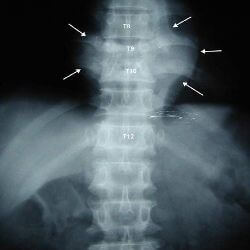

Як правило, туберкульоз хребта діагностують на спільних обстеженнях організму. Основний метод його виявлення — за допомогою рентгена. Його застосовують для виявлення вогнищ туберкульозу у всіх органах. Для діагностики цього виду використовують рентгенографію грудної клітки. Вона демонструє наявність вогнищ в легенях, лімфатичних вузлах, хребті і всіх кістково-суглобових тканинах. З розвитку кальцинації визначають давність вогнищ туберкульозу.

Для визначення стадії розвитку туберкульозу проводять додаткову рентгенографію самого хребта. На ранніх стадіях вона показує виразно звуження відстані між хребцями, показує наявність зміненої структури кісткової тканини всередині них, або окружної області.

На пізніх стадіях рентген показує викривлення хребта в кутастої форми. Якщо є гнійні скупчення у формі абсцесів, на знімку видно щільні вузлуваті ділянки у вигляді тіні, які можуть бути оточені тонкими смужками і кальциновані освіти. Для діагностики абсцесів застосовують МРТ хребта.

У цілому діагностика базується на рентгенівському випромінюванні області тулуба. Зазвичай при виявленні туберкульозу в організмі, проводять його комплексне обстеження на виявлення суміжних осередків захворювання. Паралельно проводиться аналіз крові і біопсія на наявність туберкульозної палички.